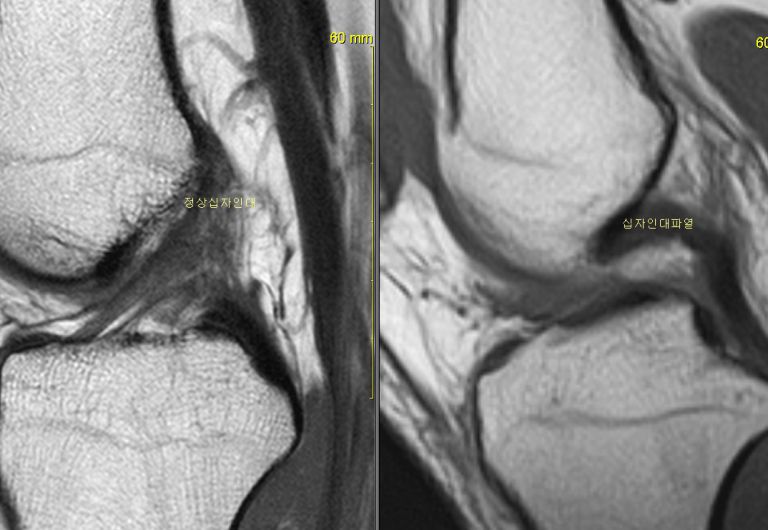

전방십자인대파열 MRI 결과비교